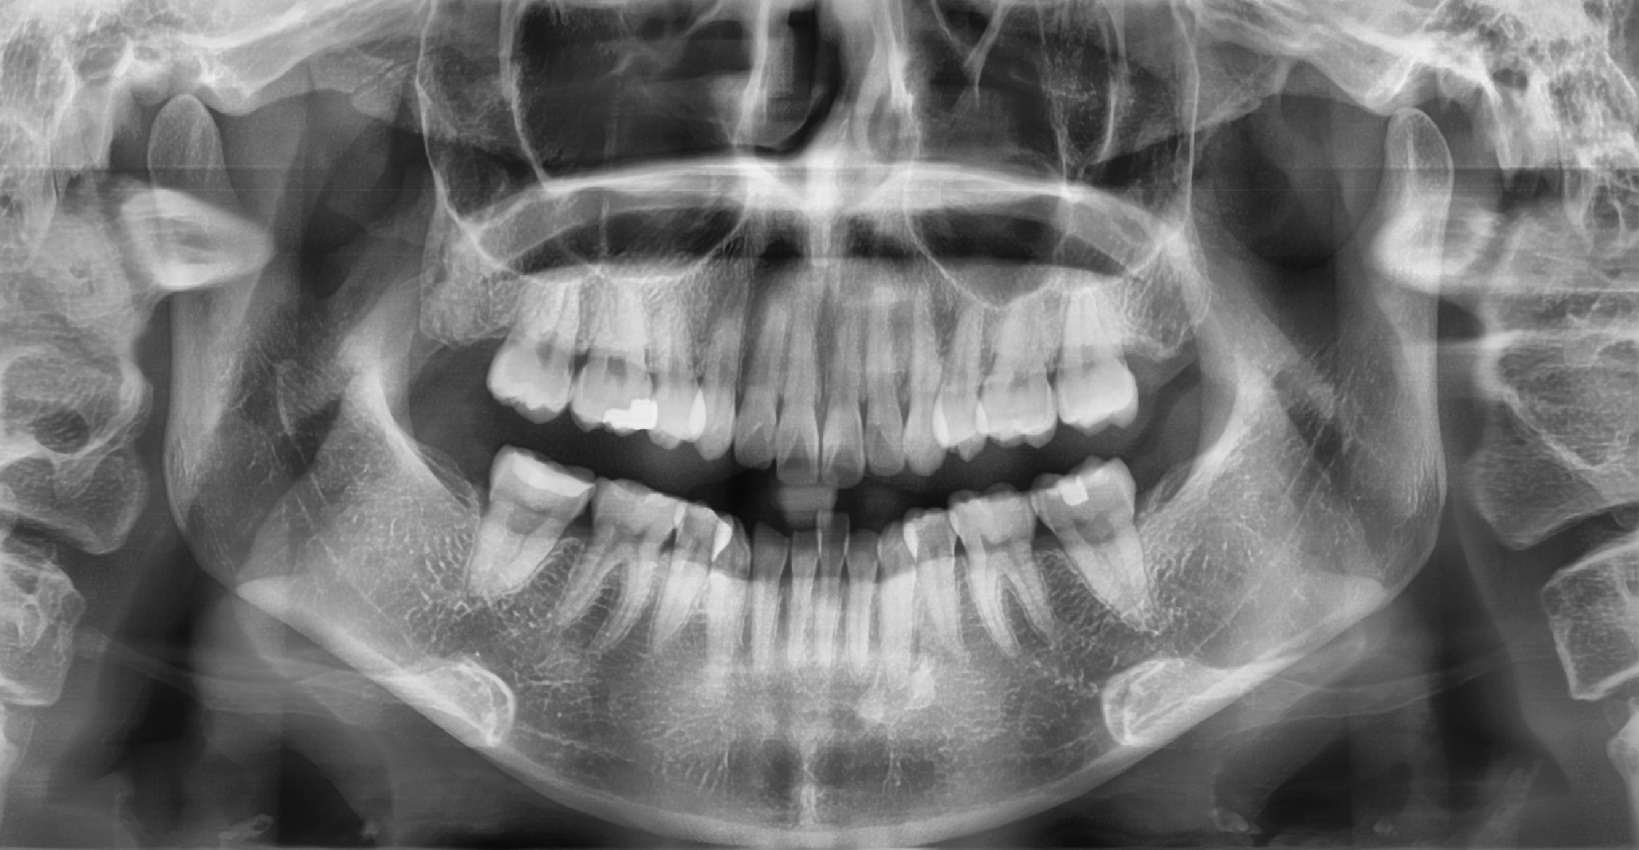

1. 파노라마 사진 ( 위아래 턱이 한꺼번에 나와서 사진 하나에 치아가 모두 찍히는 사진 )만 보며 설명 할 뿐 의사가 탐침으로 입 안을 살피지 않는 경우 패스합니다.

일단 엑스레이를 찍는 이유는 치아와 치아가 붙은 그 사이를 육안으로 확인하기 어려운 경우에 도움을 받으려고 찍거나 치아 뿌리의 상태를 확인하기 위해서 찍습니다.

치아 윗면이나 옆면은 직접 입 안을 살펴보고 탐침으로 건드려보고 하면 견적이 나옵니다.

게다가 파노라마 사진의 경우 이것만으로는 치아 사이의 충치를 완벽히 발견 할 수 조차 없습니다.

치아 사이의 충치를 제대로 확인하려면 교익 방사선 사진이 필요합니다.